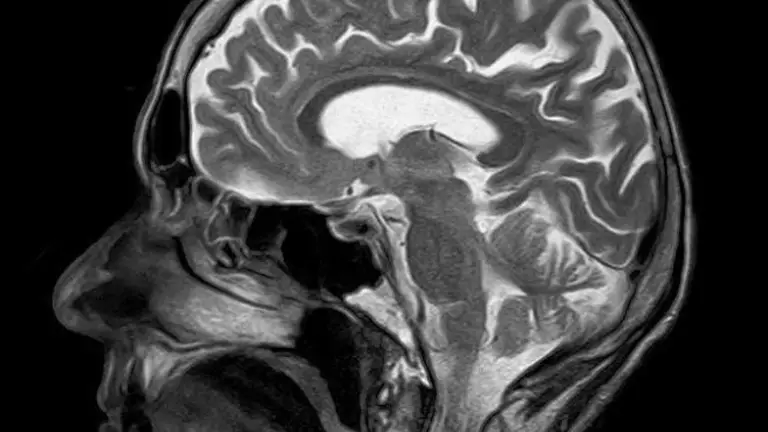

Un estudio proteómico realizado por primera vez en la amígdala cerebral humana por investigadores del grupo de Neuroplasticidad y Neurodegeneración de la Universidad española de Castilla-La Mancha (UCLM, centro del país), revela que esta región es clave en el progreso del alzheimer.

El estudio se centró en la amígdala cerebral humana, región que recibe ese nombre por su forma de almendra.

Este es muy importante en el funcionamiento cerebral, ya que está altamente conectada con las funciones conscientes que procesa fundamentalmente la corteza y las respuestas autónomas, y es primordial en el control de las emociones.

La investigación, que ha sido publicada en Brain Pathology, -revista oficial de la Sociedad Internacional de Neuropatología financiada por la UCLM y los gobiernos regional y español-, revela una importante pérdida de volumen de la amígdala cerebral humana en el grupo de pacientes con alzheimer.

Sin embargo, esa reducción no estaba relacionada con la pérdida de neuronas a pesar de la gran cantidad de depósitos de marcadores patológicos.

Por el contrario, sí detectó un aumento importante de las células de glía (del sistema nervioso) asociadas a la inflamación de la región de la amígdala.

Este trabajo es uno de los primeros análisis proteómicos de la amígdala humana en la enfermedad de Alzheimer y permitió identificar más de 2000 proteínas, algunas de las cuales, tras distintos análisis bioinformáticos, constituyen potenciales biomarcadores de la enfermedad que ayudarán a su diagnóstico y tratamiento.